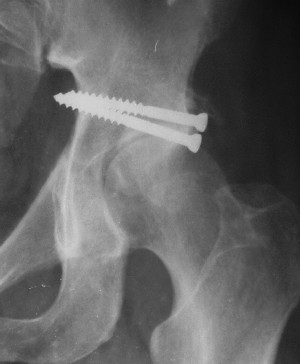

Больной 18 мая 2003 года в автоаварии получил перелом левой вертлужной впадины, вывих бедра. Госпитализирован в один из стационаров области.Вывих вправлен. В последствии бедро вывихивалось еще дважды. На консультацию был представлен снимок от 19.05.03г., больной переведен к нам 3.06.03г. Снимок при поступлении - перелом впадины, задне-верхний вывих бедра. 05.06.2003 г. выполнено открытое вправление вывиха левого бедра и остеосинтез стенки вертлужной впадины двумя винтами. Послеоперационный период без осложнений. Объем движений в левом тазобедренном суставе восстановился полностью. Выписан на амбулаторное лечение в удовлетворительном состоянии с рекомендациями 3 месяца ходить на костылях без нагрузки на оперированную конечность. На контрольных рентгенограммах левого тазобедренного сустава 13.10.2003 г. - признаки консолидации перелома; плотность, форма головки и состояние суставных поверхностей удовлетворительные. Разрешена дозированная осевая нагрузка, на конечность с использованием дополнительной опоры. 19.12.2003 г. больной обратился с жалобами на боли в левом тазобедренном суставе. На рентгенограммах левого тазобедренного сустава 19.12.2003 г., 20.02.04г. - асептичекий некроз головки бедра. 5.04.04г. - эндопротез. Сейчас ходит без трости, не хромает. Особенность эндопротезирования - при удалении винтов прослежена линия перелома заднего края впадины и предложено установить чашку несколько меньшего диаметра, чтобы она была покрыта несломанной частью.